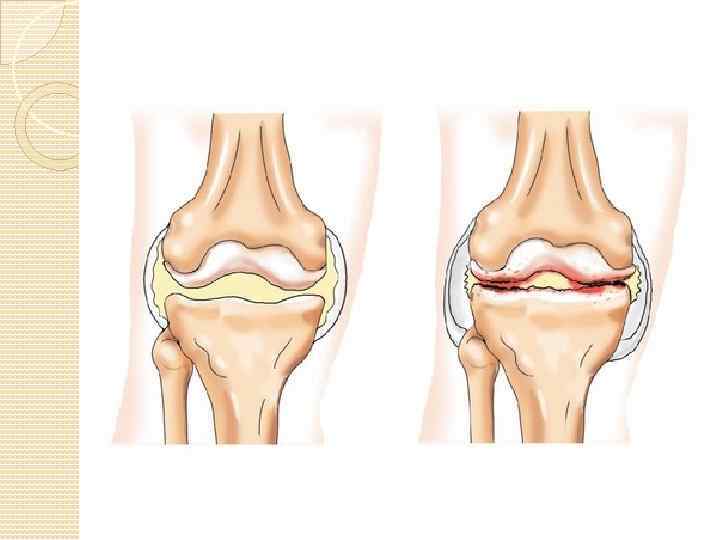

АРТРОЗ Артроз – это дегенеративнодистрофическое поражение сустава, захватывающее главным образом хрящ, эпифизы костей и в меньшей степени мягкие ткани. Артрозы различают первичный и вторичный. Первичный артроз развивается в неизмененном ранее суставе. Вторичный артроз – проявляется на почве предшествовавших заболеваний и патологических состояний сустава.

ГОНАРТРОЗ (АРТРОЗ КОЛЕННОГО СУСТАВА) Гонартроз (артроз коленного сустава) – в группе артрозных поражений суставов лидирует по частоте возникновения заболевания.

ОСТЕОАРТРОЗ Остеоартроз — заболевание, при котором изменения дегенеративного характера возникают в суставном хряще